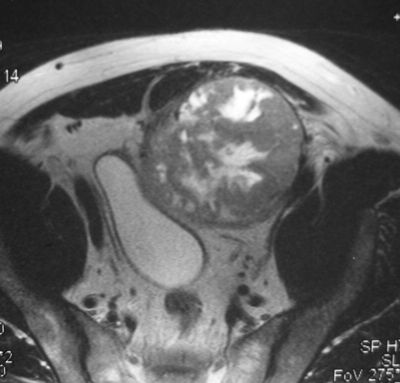

Предпузырная саркома